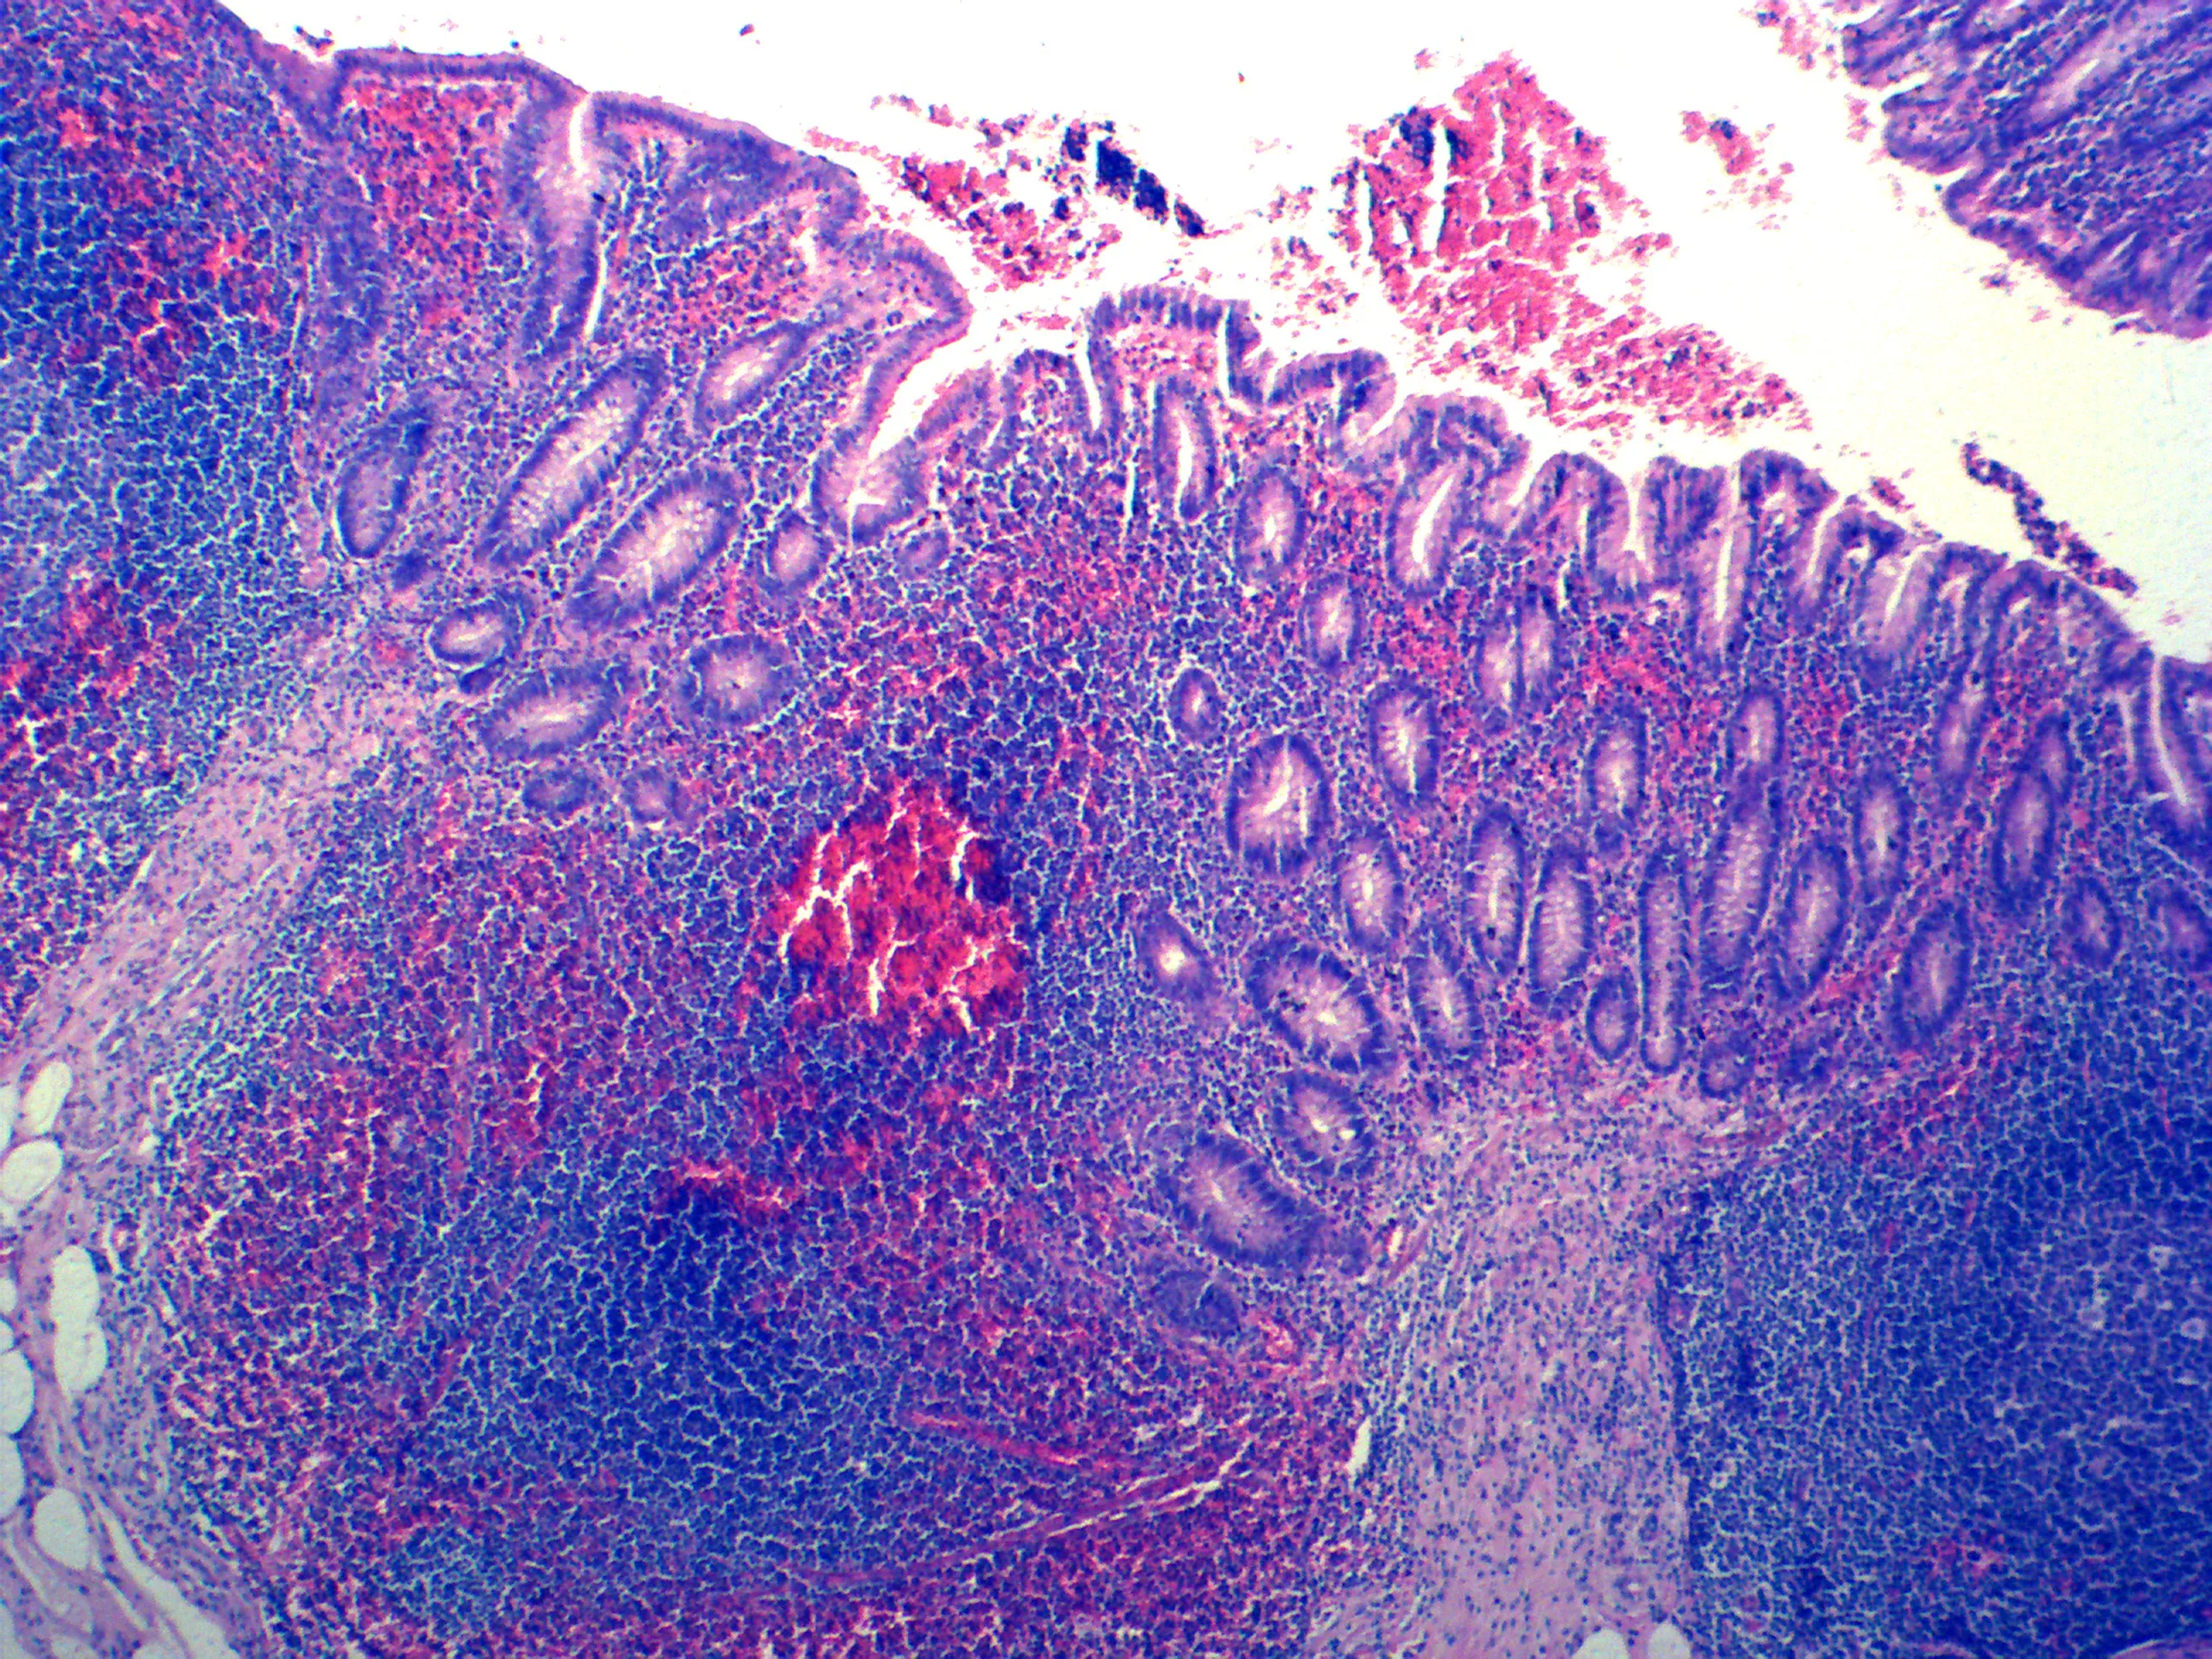

Гематоксилин майера

Гематоксилин майера 104 фотографий